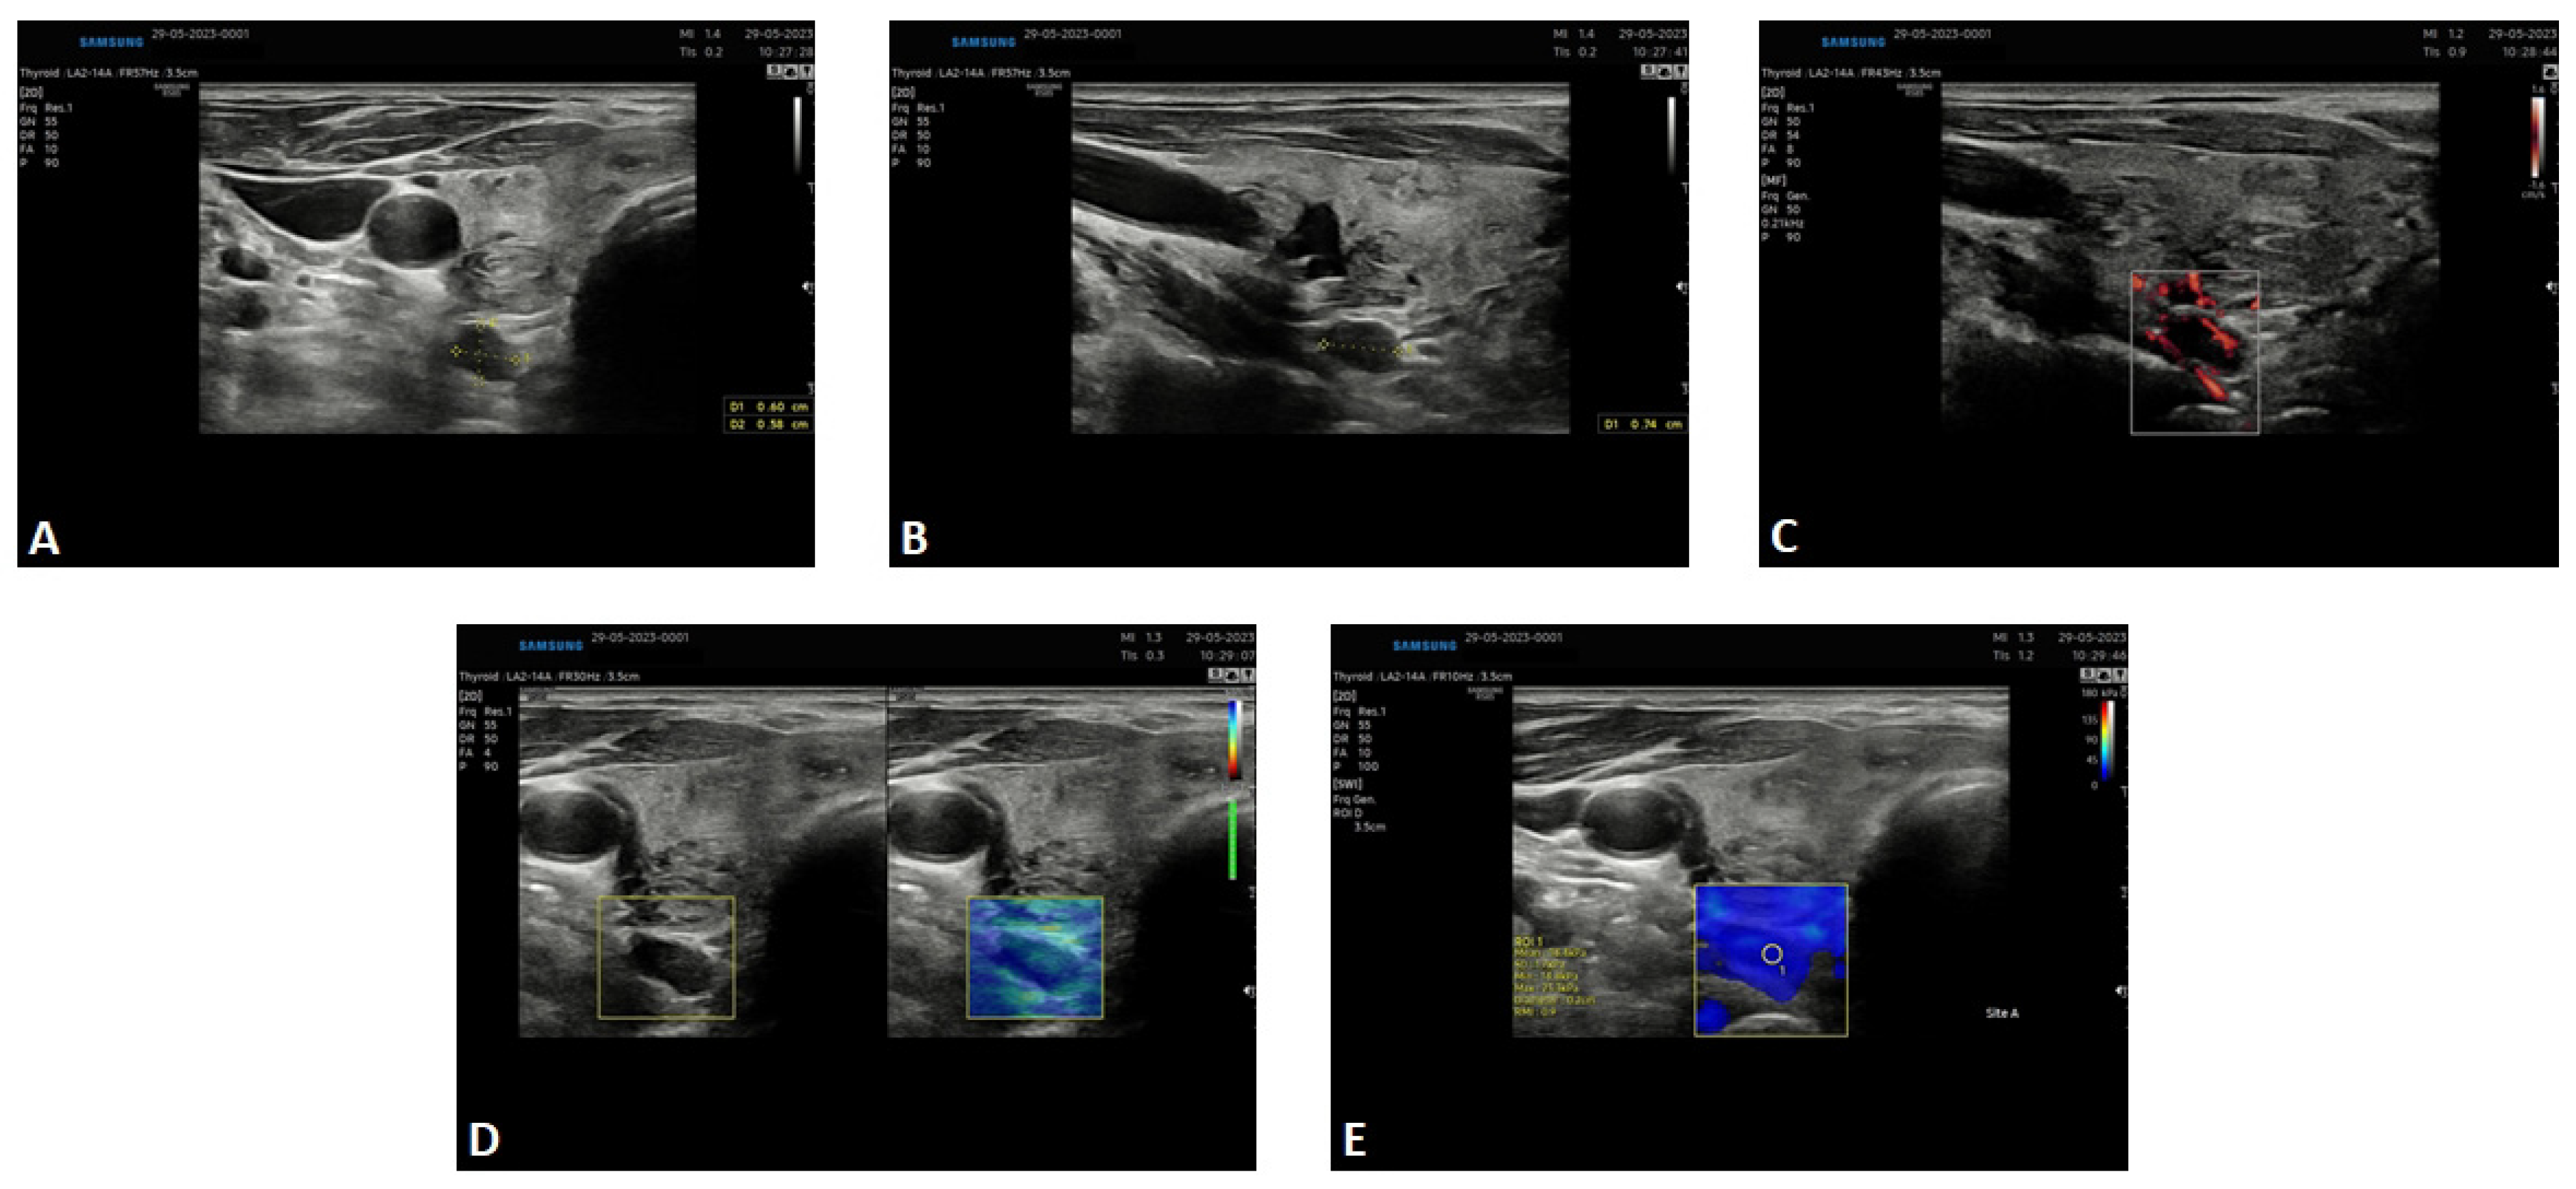

2. Results—Case Presentation